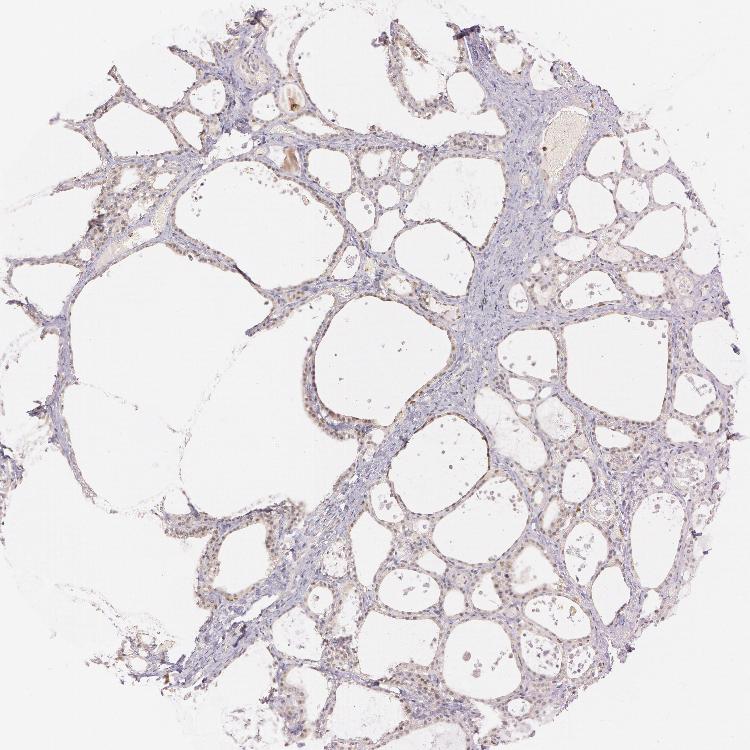

TISSUE PRIMARY DATA THYROID GLAND Show tissue menu

THYROID GLAND - Antibody stainingi

Antibody staining in the annotated cell types in the current human tissue is reported as not detected, low, medium, or high, based on conventional immunohistochemistry profiling in selected tissues. This score is based on the combination of the staining intensity and fraction of stained cells.

Each image is clickable and will lead to virtual microscopy that enables deeper exploration of all samples and also displays staining intensity scores, fraction scores and subcellular localization as well as patient and tissue information for each sample.

Antibody HPA001427Antibody HPA019665

Glandular cells LowNot detected